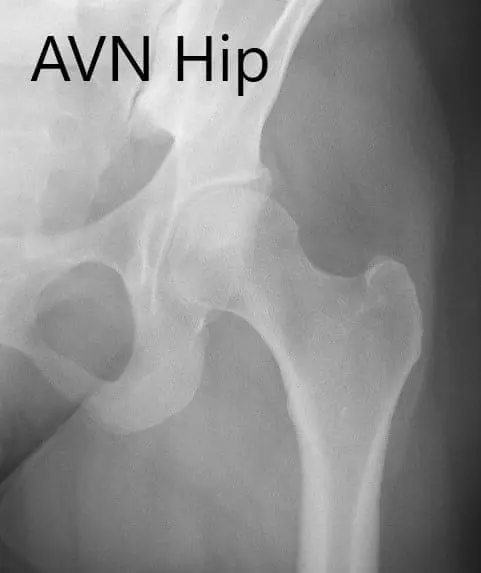

Anteroposterior view of the left hip showing pre-collapse avascular necrosis of the left hip.

Anteroposterior view of the left hip showing pre-collapse avascular necrosis of the left hip.